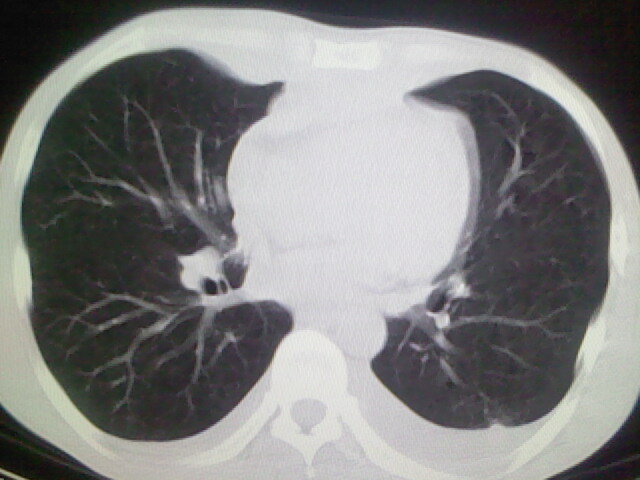

以下是引用杀毒软件在2008-9-3 6:11:00的发言:[br]侵袭性胸腺瘤------一般不侵到气管旁[br][br]考虑----纵隔淋巴瘤,心包及胸膜受累

以下是引用随光逐影在2008-9-3 7:07:00的发言:[br]1)考虑淋巴瘤可能。2)双侧胸腔积液(以左侧为甚)。3)心包积液。